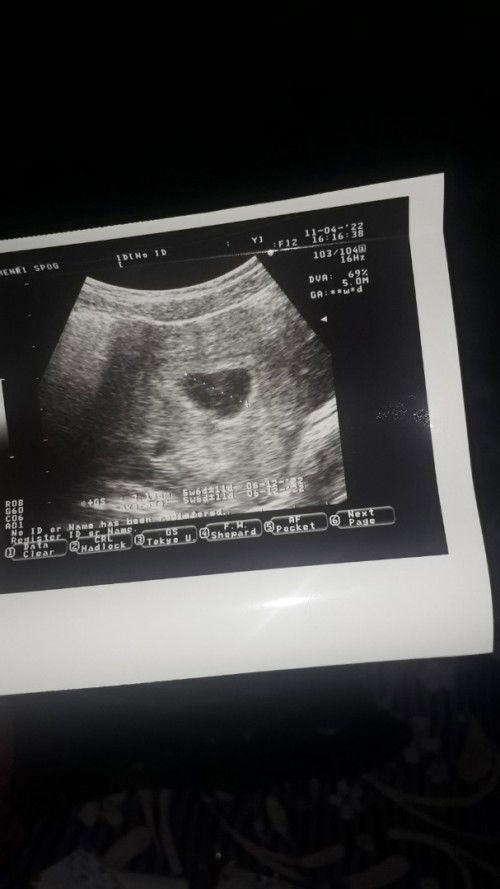

Bun mau tanya kenapa yaa uk di usg sama uk dihitung dari hpht kok beda,, Sedikit cerita jadi gini bun selama 3 hari aku keluar darah kayak orang haid tapi gk ada keluhan sama sekali udah priksa ke bidan dan disuruh usg ke dokter spesalis kandungan tapi pas usg katanya belum ada janinya🥺dari hitungan hpht usia kandungan ku 9 w 1d tapi diusg usianya 5w 1d mungkin ada yang sama an,,#bantusharing aku sedikit agak cemas bun karna cuma dua kemungkinan kalau gk hamil kosong ya janin tidak berkembang🥺